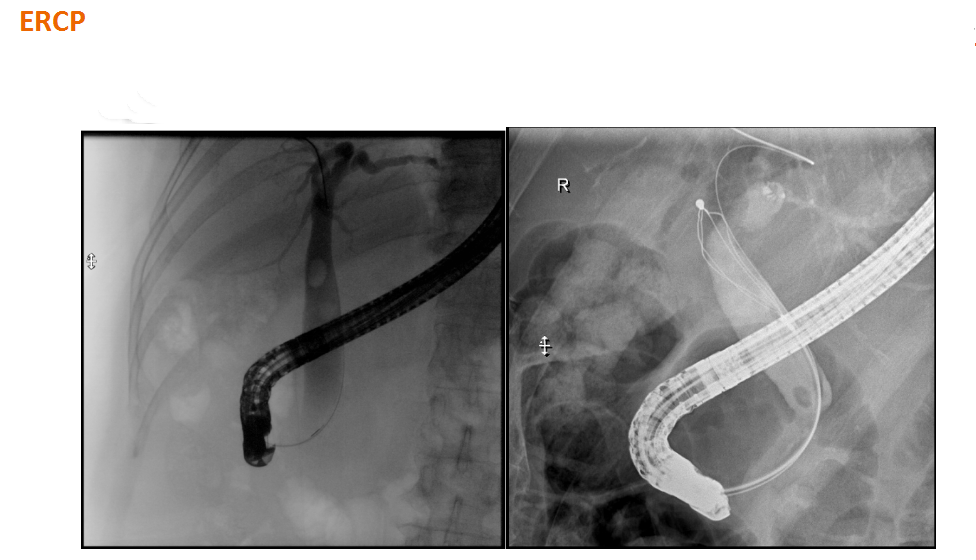

该设备属于多功能X线机,除具有传统数字胃肠机所有功能外,还有DR平板探测器X线摄影所有功能,主要用于消化道气钡双重对比造影、全脊柱拼接摄影、全下肢拼接摄影、ERCP、泌尿系造影、“T”管造影、钡剂灌肠、四肢造影、子宫输卵管造影等各类检查,是检查消化道溃疡、肿瘤、异物等疾病的主要方法之一。